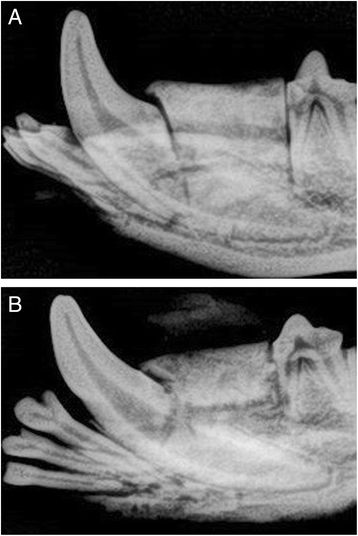

Radiographic examination revealed clear margins separating newly inserted scaffolds from surrounding bone defect (Fig. 4a). After completion of healing time, the margins between the scaffold and bone defect became less demarcated due to deposition and ingrowth of new bone (Fig. 4b).

Fig. 4

a Peri-apical X-ray of zirconia scaffold immediately placed in bone defect. Margins between scaffold and bone are clearly demarcated. b Peri-apical X-ray of zirconia scaffold after completion of healing time. Margins between bone defect and scaffold are less demarcated due to new bone growth